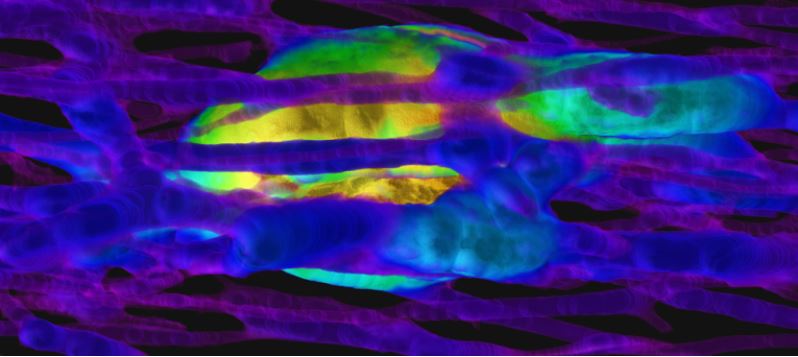

This image is a finalist in the #ScienceExposed photo competition run by @NSERC_CRSNG. The snapshot, titled "A living record," was submitted by CLS user Janna M. Andronowski @MemorialU. Learn about the image and vote for it at: https://t.co/2YEDuLJXYg

Thanks for the support, @InnovationMUN! Check out our @NSERC_CRSNG #ScienceExposed bone biology-inspired image below and give us a vote! 🔬🦴

I am excited that an image submitted from our #bonebiology research has been included in the top 20 finalists for the @NSERC_CRSNG #ScienceExposed 2023 competition! Voting is now open, if you like it, cast your vote via the link below! https://t.co/GZWpQKXmRE

Voting is now open for @NSERC_CRSNG's #ScienceExposed! Be sure to vote for Dr. Janna M. Andrownowski's entry: A Living Record which features a high-resolution 3D render of bone. https://t.co/fDijbaI0K2 @AndronowskiLab @Dolores_McKeen @MemorialU @munmgss @MUNMedSoc @Memorialu

Our March issue is out! The cover article describes a new multimodal 3D imaging approach of pore networks in the human femur by Janna Andronowski @AndronowskiLab et al.: https://t.co/ePdS7q0coG

Hot off the presses @AnatRecord! New article employing high-res 3D imaging (@CanLightSource) of age & sex-related differences in femoral cortical porosity & lacuno-canalicular microarchitecture. Big shout out to all hard working trainees who contributed! Link to article👇:

Interdisciplinary work by @AndronowskiLab et al. leverages bone biology & high-resolution 3D imaging to comprehensively characterize age & sex-associated differences in cortical porosity & Lacuno-Canalicular Network (LCN) architecture in the human femur: https://t.co/jqZr4k839Y